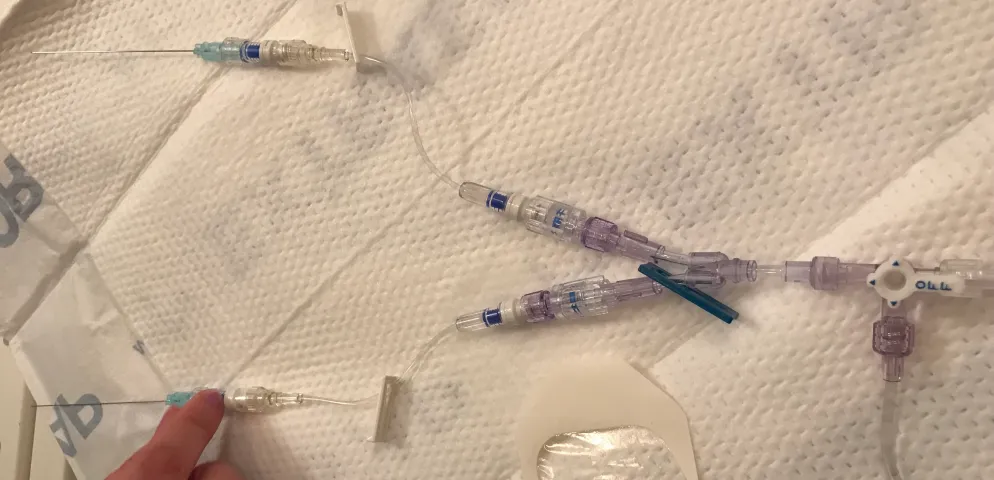

DCMRL was developed approximately five years ago in order to image the central lymphatic system in a way similar to the intranodal lymphangiography1,2. It is performed by placing of the small needles into the groin lymph nodes. It is usually performed outside the room where is the MR magnet is located. It is much easier to do when MR equipped with detachable table. The table detached, moved in the prep area and the needle are inserted.

To confirm the position of the needles we usually inject the US contrast (Sonovue, Bracco Monroe Township, NJ) through the needles. The proper position is confirmed, when the draining lymphatics ducts are enhanced3(Movie).